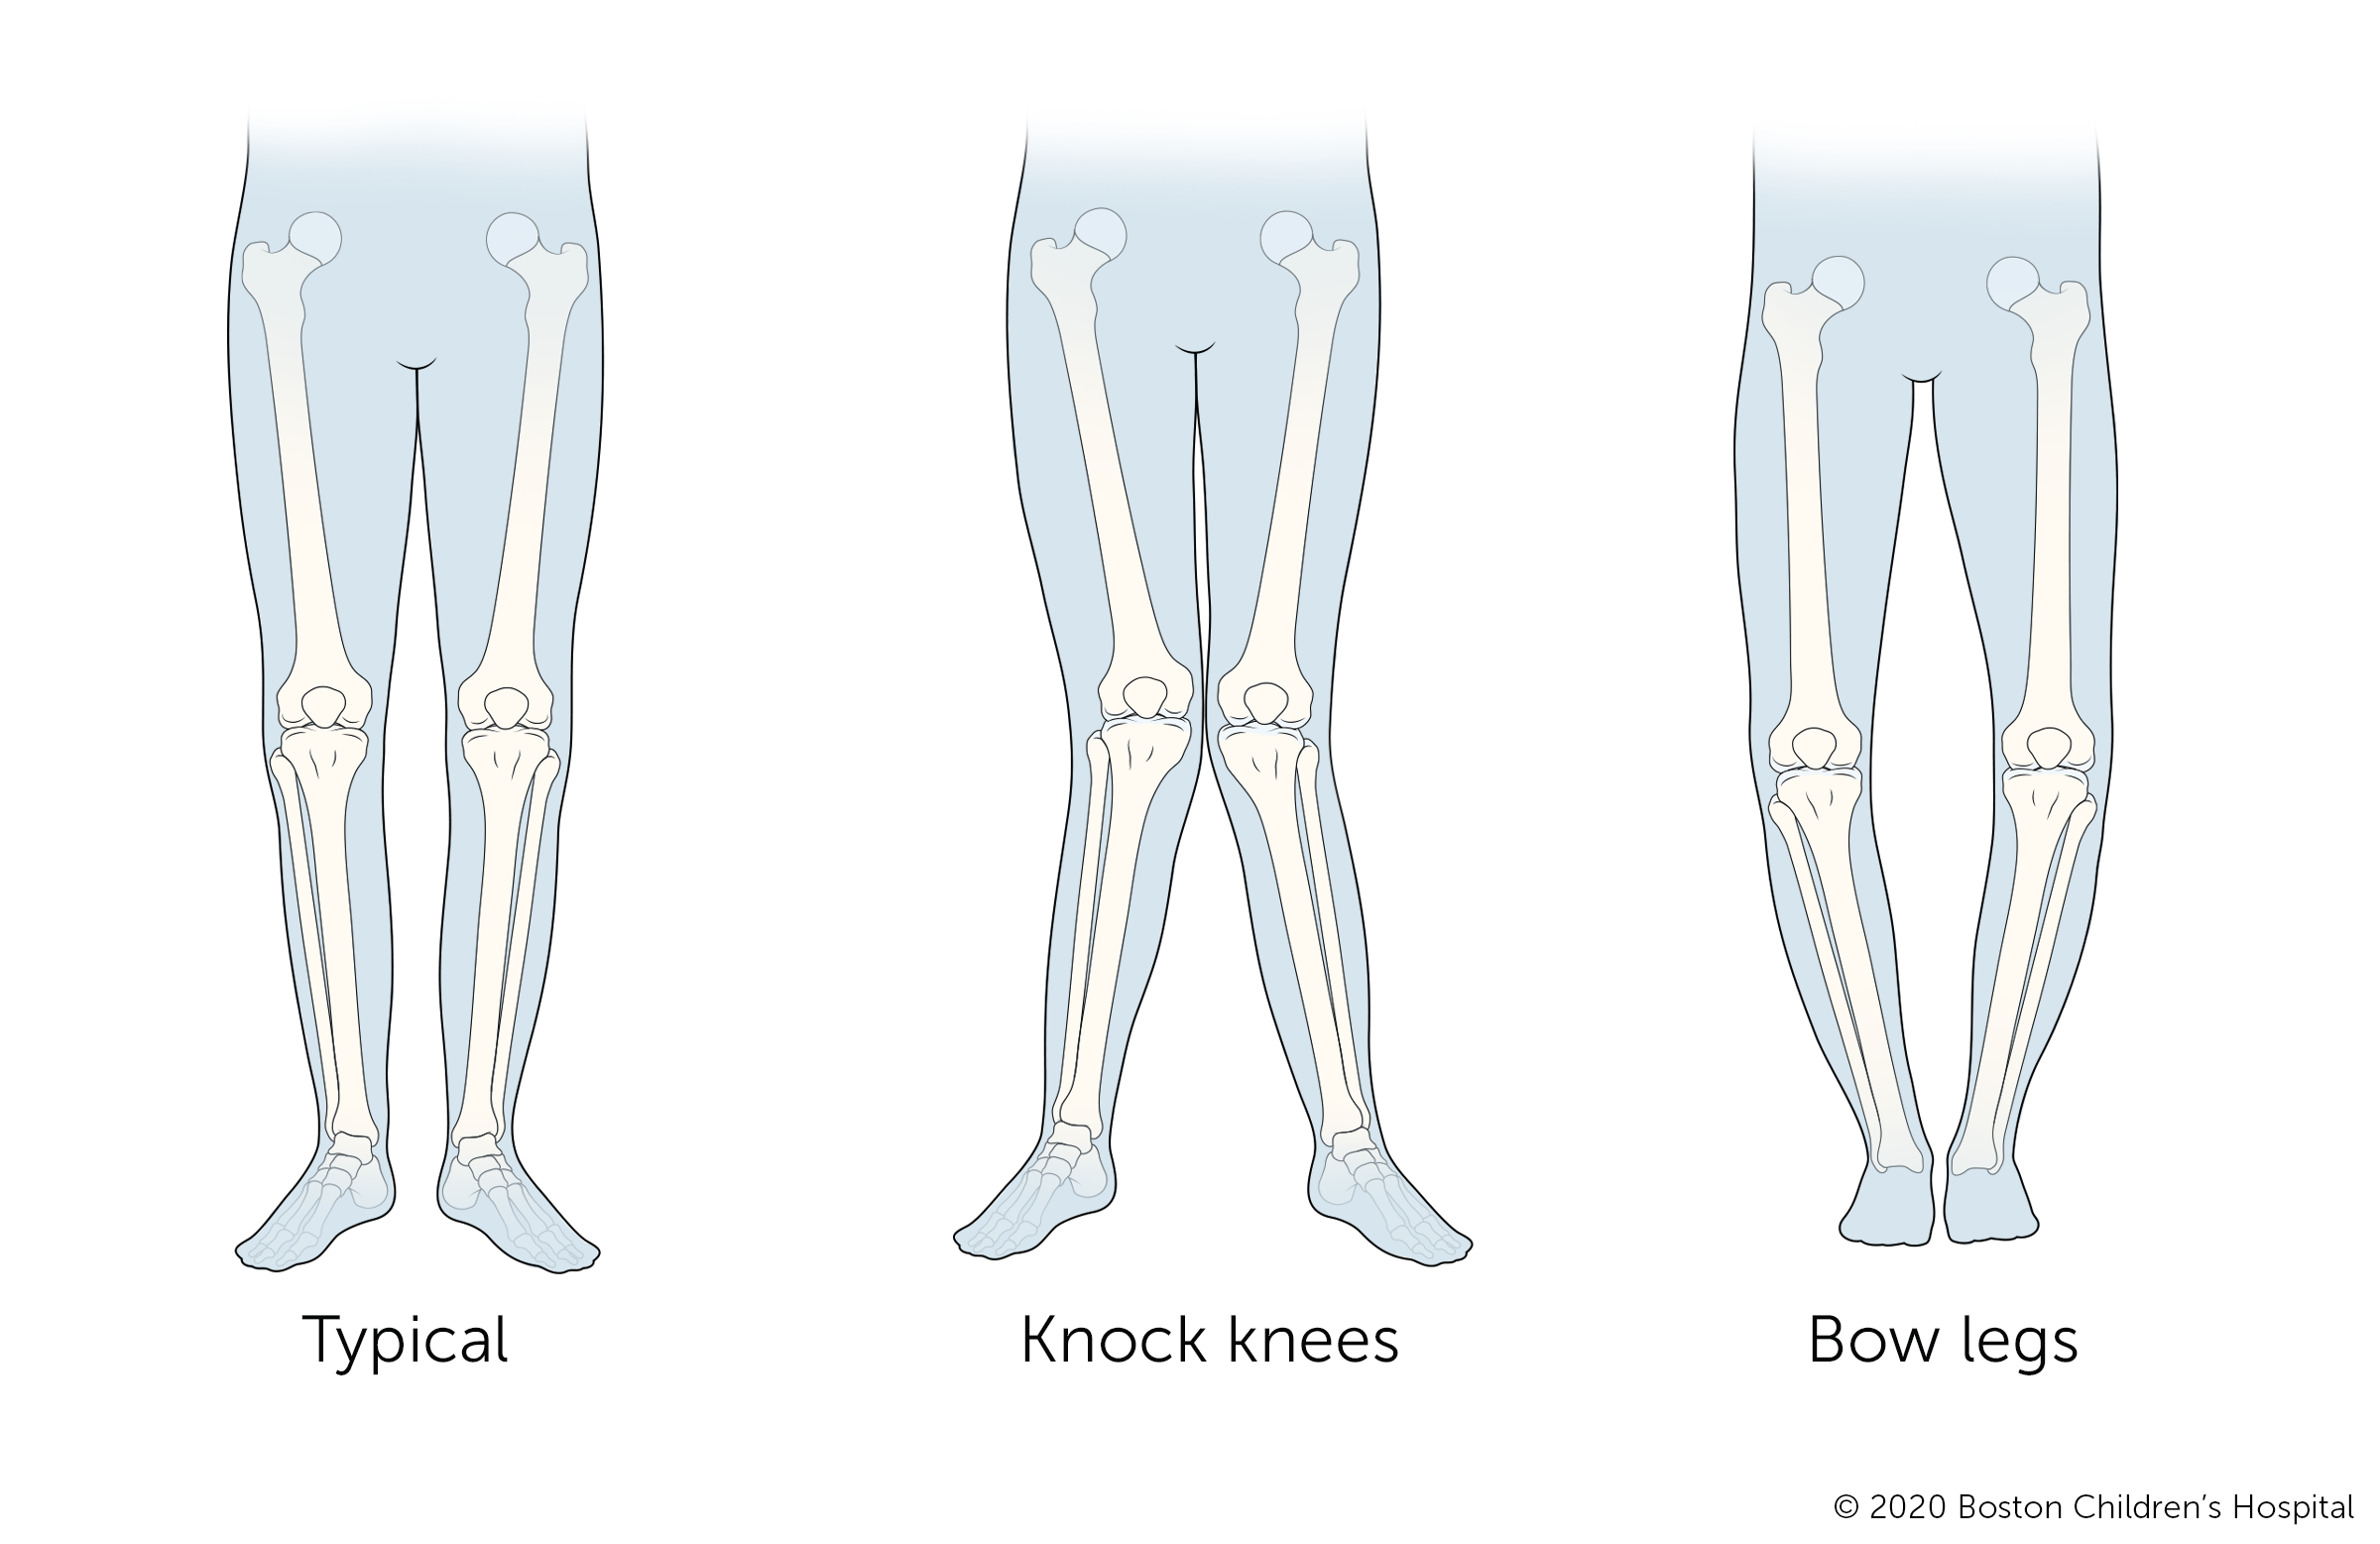

Bowlegs and knock knees

Bowlegs is an outward curve of the legs at the knees. Knock knees is an inward curve of the legs at the knees. Both bowlegs and knock knees are common stages of development and usually self-correct as a child grows.